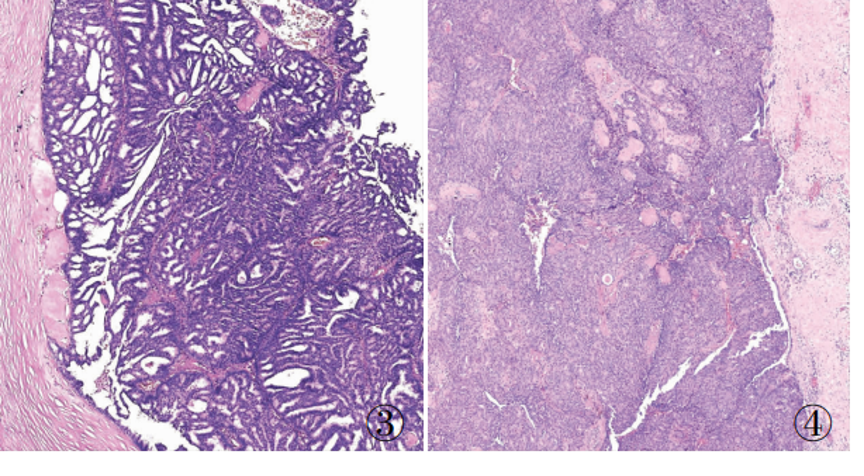

原位SPC:轮廓光滑的圆形结节结节周围无促结缔组织增生结节周围肌上皮可有可无

浸润癌两种浸润方式

1、浸润性实性乳头状癌:保留实性乳头状结构,体积大的团巢,轮廓不规则,间质促纤维反应,肌上皮缺失,原位SPC背景

2、实性乳头状癌伴浸润:轮廓圆滑的结节,伴有浸润性成分,包括粘液癌,NET,浸润性癌(NST)

原位SPC的乳头轴心及导管周边的肌上皮可以存在,也可以不同程度减少。原位SPC可被视为导管原位癌的特殊亚型,因此,临床可以按导管原位癌处理。极端状态下,导管周边的肌上皮可以完全缺失,此时可被称为膨胀性或推挤性浸润,其形态与原位SPC高度相似。研究显示,膨胀性浸润的SPC通常不发生转移,因此仍可按导管原位癌处理。

当在原位SPC的背景上,部分原位SPC轮廓变得不规则,或呈地图、锯齿状,并出现促纤维反应,或浸润脂肪,可称为原位SPC伴浸润(毁损性浸润),这时需按浸润癌处理。